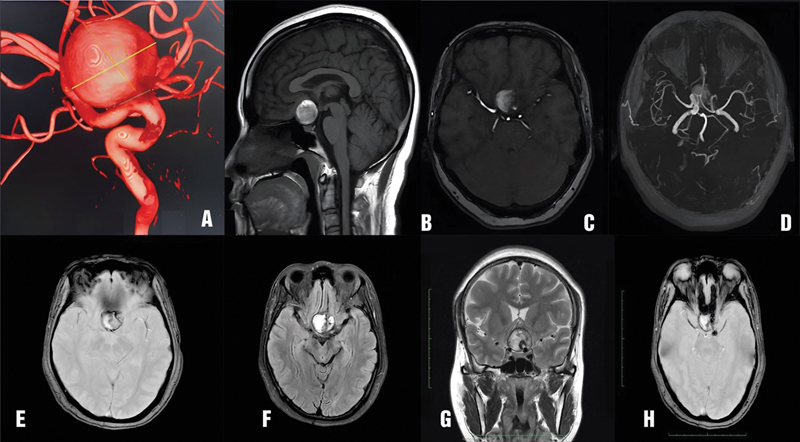

Flow diverter (FD) is often the first-line treatment for giant internal carotid artery aneurysms, with a high rate of aneurysm occlusion. However, up to 10% of giant cerebral aneurysms increase in size after FD treatment. Surgery is usually considered if the giant internal carotid artery aneurysm continues to enlarge and cause compression. We report a case of a giant internal carotid artery aneurysm that continued to increase in size after FD treatment and was subsequently treated surgically. We also review the literature on the management of giant cerebral aneurysms that increased in size after FD. A 41-year-old female patient was diagnosed with a right giant internal carotid artery aneurysm and was initially treated with FD. After FD, the patient's vision in the right eye did not improve. Despite medical treatment, her vision continued to deteriorate. The patient presented at our hospital with reduced vision in both eyes. Magnetic resonance imaging and digital subtraction angiography with balloon test occlusion confirmed the presence of a giant thrombosed aneurysm in the right internal carotid artery, compressing the right optic nerve and optic chiasm. The patient underwent external carotid artery-middle cerebral artery bypass surgery using a radial artery graft, aneurysm sac dissection with thrombus removal, and reconstructive clipping of the aneurysm neck. After surgery, the patient's vision in both eyes improved immediately and did not develop any new neurological symptoms. Extracranial-intracranial arterial reconstructive surgery is a viable option for treating giant internal carotid artery aneurysms that have undergone FD treatment but continue to present with progressive mass effects.